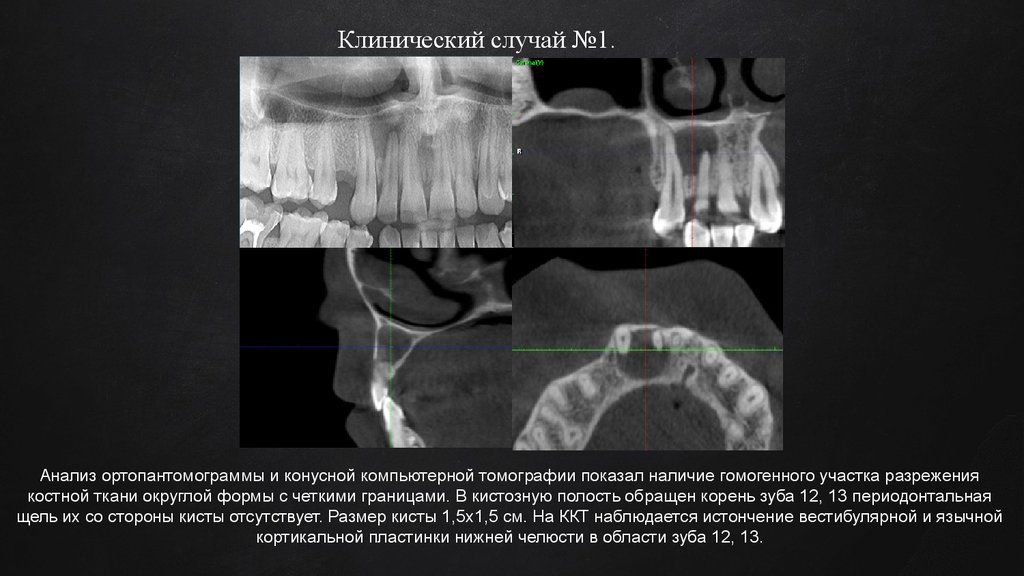

Клинический случай №1.

Анализ ортопантомограммы и конусной компьютерной томографии показал наличие гомогенного участка разрежения

костной ткани округлой формы с четкими границами. В кистозную полость обращен корень зуба 12, 13 периодонтальная

щель их со стороны кисты отсутствует. Размер кисты 1,5x1,5 см. На ККТ наблюдается истончение вестибулярной и язычной

кортикальной пластинки нижней челюсти в области зуба 12, 13.